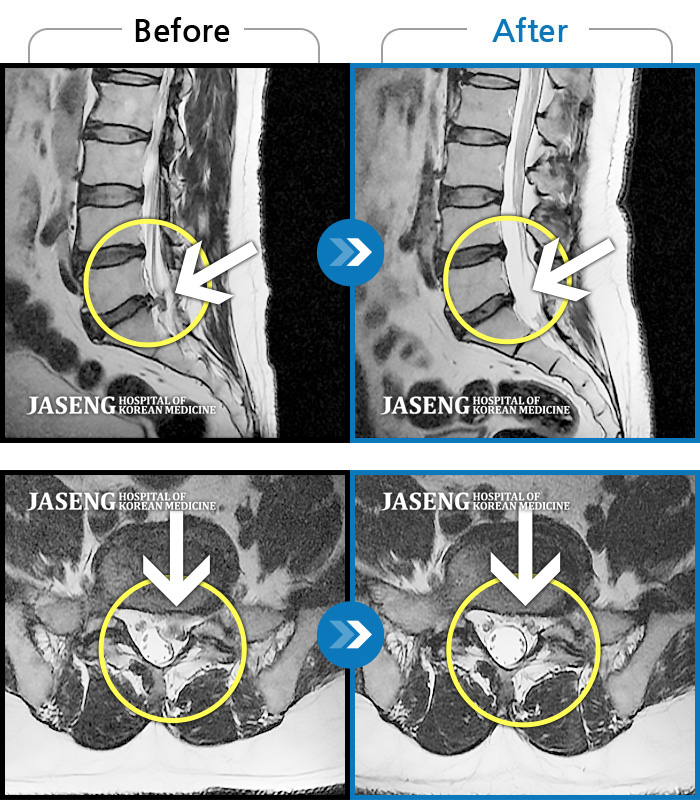

Before

After

환자에게 사전 동의를 받아 동일 조건에서 촬영되었습니다.

개인에 따라 치료 후 부작용이 발생할 수 있으니 의료진과 상담 후 치료를 진행하시기 바랍니다.

허리디스크로 인한 요통